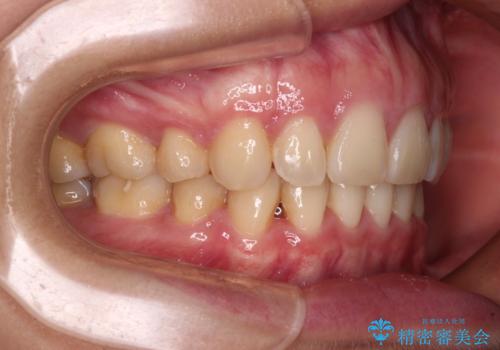

上顎前突 目立たないワイヤー装置での抜歯矯正

口元を積極的に引っ込めるために、上下左右の小臼歯計4本を抜歯することとしました。

咬み合わせが深いため、咬み合わせの高さを向上させながら口元を下げることとしました。

左右ともに下顎に対して上顎歯列が前方位にある上顎前突であったので、上顎歯列全体を後方に移動させることで上下咬み合わせを改善し、その上で抜歯矯正により口元の突出感を改善させていきました。